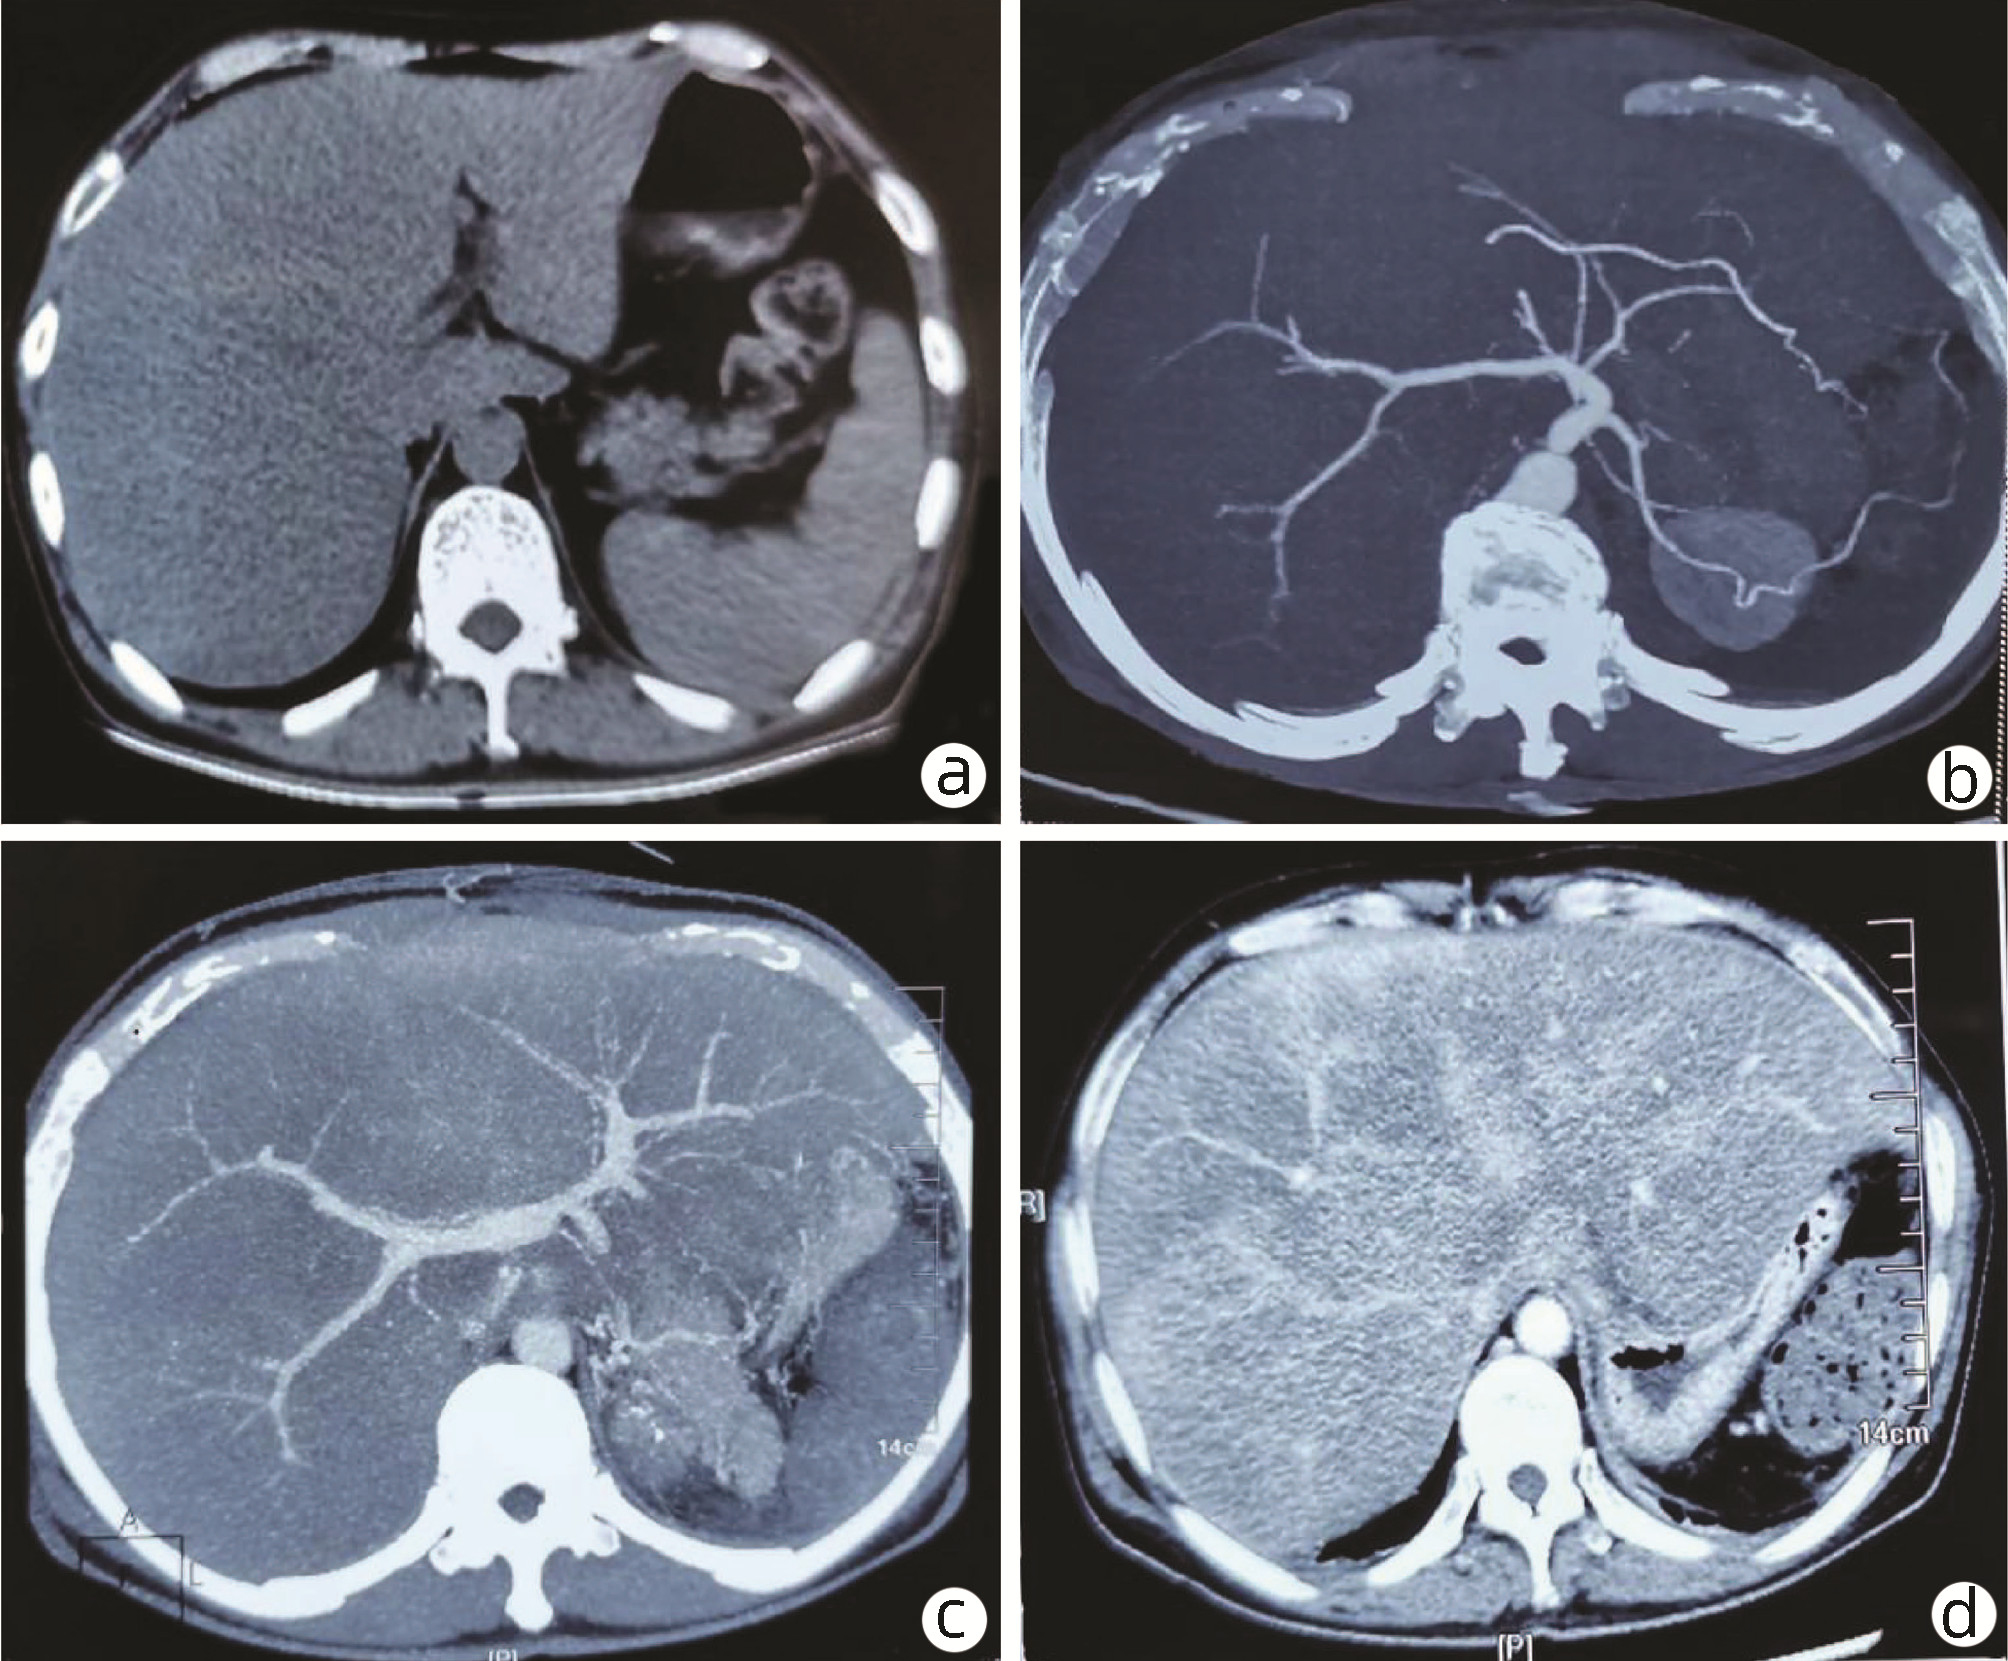

Schwannoma of the pancreatic tail: A case report

Jiachao ZHANG, Rong TANG, Zhensheng ZHANG, Pingping CHEN, Yongchao ZENG

2022, 38(8): 1878-1879. DOI: 10.3969/j.issn.1001-5256.2022.08.030

Abstract(619) HTML (265) PDF (3067KB)(50)

Abstract: